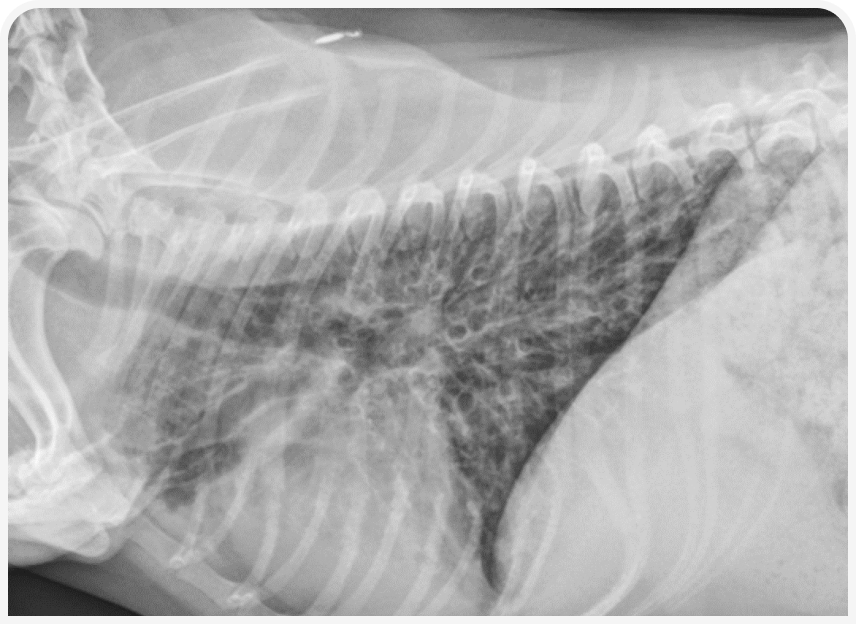

При рентгенографии органов грудной клетки у собак с бронхитом можно выявить бронхиальный тип легочного рисунка (Рисунок 2) или увеличение количества и толщины стенок дыхательных путей, но в некоторых случаях данные рентгенографии могут оказаться относительно неинформативными.

Бронхоэктазы характеризуются расширением стенок и отсутствием нормального сужения дыхательных путей к периферии (Рисунок 3), однако рентгенография для подтверждения этого состояния относительно малочувствительна. Более чувствительна для оценки диаметра дыхательных путей компьютерная томография, позволяющая описать распространенность заболевания.